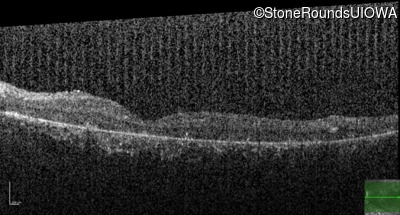

Age at visit: 8 years (Visit 2)

Age at visit: 9 years